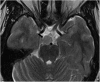

Hamartomas are tumours composed of mesenchymal tissues such as cartilage, fat, connective tissue and smooth muscle and can be found in virtually any organ system. These masses commonly develop sporadically, but are also seen in certain syndromes such as tuberous sclerosis or Carney triad. While their imaging appearance varies depending on the organ they arise from, findings are usually unique and a diagnosis can be confidently made. Radiologists must be aware of the clinical and imaging presentations of these lesions with the particular goal of avoiding unnecessary studies or invasive procedures. Furthermore, knowledge of common syndromic entities is crucial, as the radiologist may be the first to suggest the diagnosis.